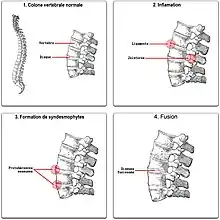

À terme (plusieurs années d’inflammation), les enthèses, c'est-à-dire les tendons, les ligaments, les capsules — ce qui est autour de l’articulation — vont se calcifier jusqu'à s'ossifier. Dans les formes extrêmes, cela peut constituer des ponts osseux surtout au rachis, mais parfois aussi aux épaules ou aux hanches. Ce type d'atteinte est qualifiée d'historique car se voyant surtout avant les années 1960. Néanmoins, il arrive de voir ce type d'atteinte encore de nos jours.

Au niveau des articulations sacro-iliaques, il y a une fusion entre les deux os, le bassin et le sacrum, et surtout entre les vertèbres. Ces fusions s’appellent des syndesmophytes. L'évolution peut se poursuivre vers une forme ankylosante, c’est-à-dire à une inflammation suffisamment sévère pour occasionner des enraidissements.

Dans les formes les plus évoluées, il peut y avoir une ossification complète avec soudure de tous les os concernés : les vertèbres lombaires forment un seul bloc. Cela arrive au niveau du dos mais aussi au niveau du cou.

De temps à autre surgissent des douleurs importantes qui alternent avec des épisodes indolores. Généralement survient la formation des calcifications des ligaments d'une articulation et plus particulièrement des ligaments se trouvant en avant et sur les côtés permettant l'union des vertèbres, entraînant ce que l'on appelle la pelvispondylite rhumatismale. Celle-ci génère des déformations caractéristiques de la colonne vertébrale. Progressivement, la lordose — le creusement des reins — disparaît et les muscles constituant les fesses fondent. Au niveau du thorax en arrière, la cyphose — l'arrondi du thorax — est accentuée : accentuation de la bosse thoracique. Quand il existe une atteinte du rachis cervical, la tête semble comme projetée vers l'avant. L'atteinte de la hanche entraîne une ankylose pouvant conduire à une flexion de celle-ci, compensée par une flexion des genoux.